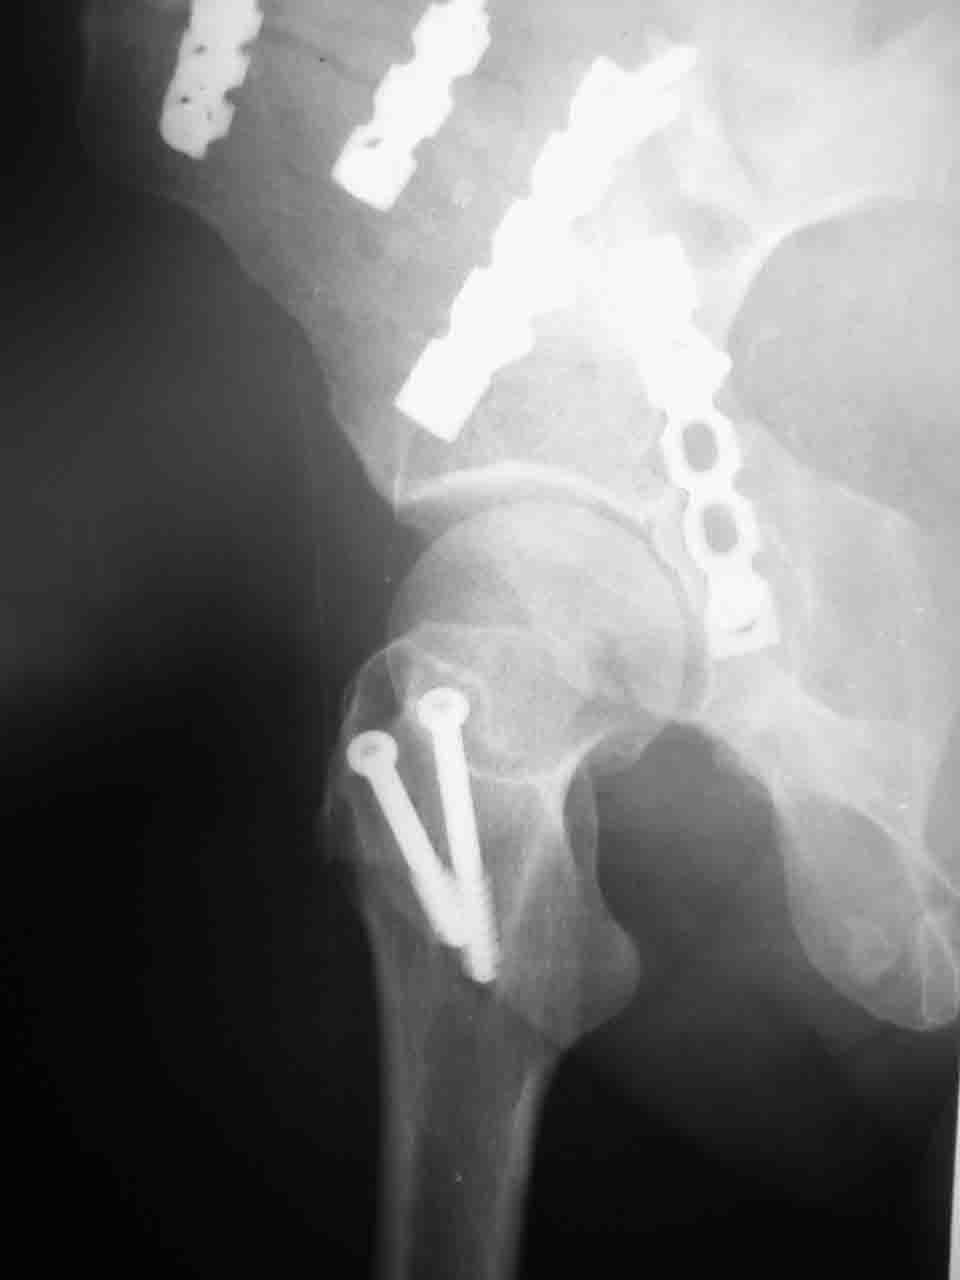

Спасибо за комментарии и рекомендации. Откровенно говоря, больного я прооперировал на прошлой неделе, через 5 дней после аварии и проблем с ним пока никаких нет, на удивление при достаточно обширной диссекции (илиофеморальный доступ) болей практически нет, так что больной самостоятельно садится в кровати, выполняет активные движения в оперированном суставе, сгибая до 60 градусов пока, далее с ассистенцией.

Причиной обращения к сообществу были возникшие непосредственно после операции сомнения и разочарования полученным качеством репозиции: а надо ли было трогать перелом вообще, репозиция передней колонны технически была очень сложна для меня, хотя реконструкции была в той же последовательности, что Д-р А.В.Рунков рекомендовал, в какой-то момент безуспешных манипуляций стал думать о *вторичной конгруэнтности*, которую не так давно обсуждали на

форуме и скелетном вытяжении. С репозицией и фиксацией задней колонны и отдельно задне-верхней стенки впадины проблем не возникло. Послеоп. Рг граммы в приложении. Если возникнут какие-либо дополнения или поправки - был бы признателен.